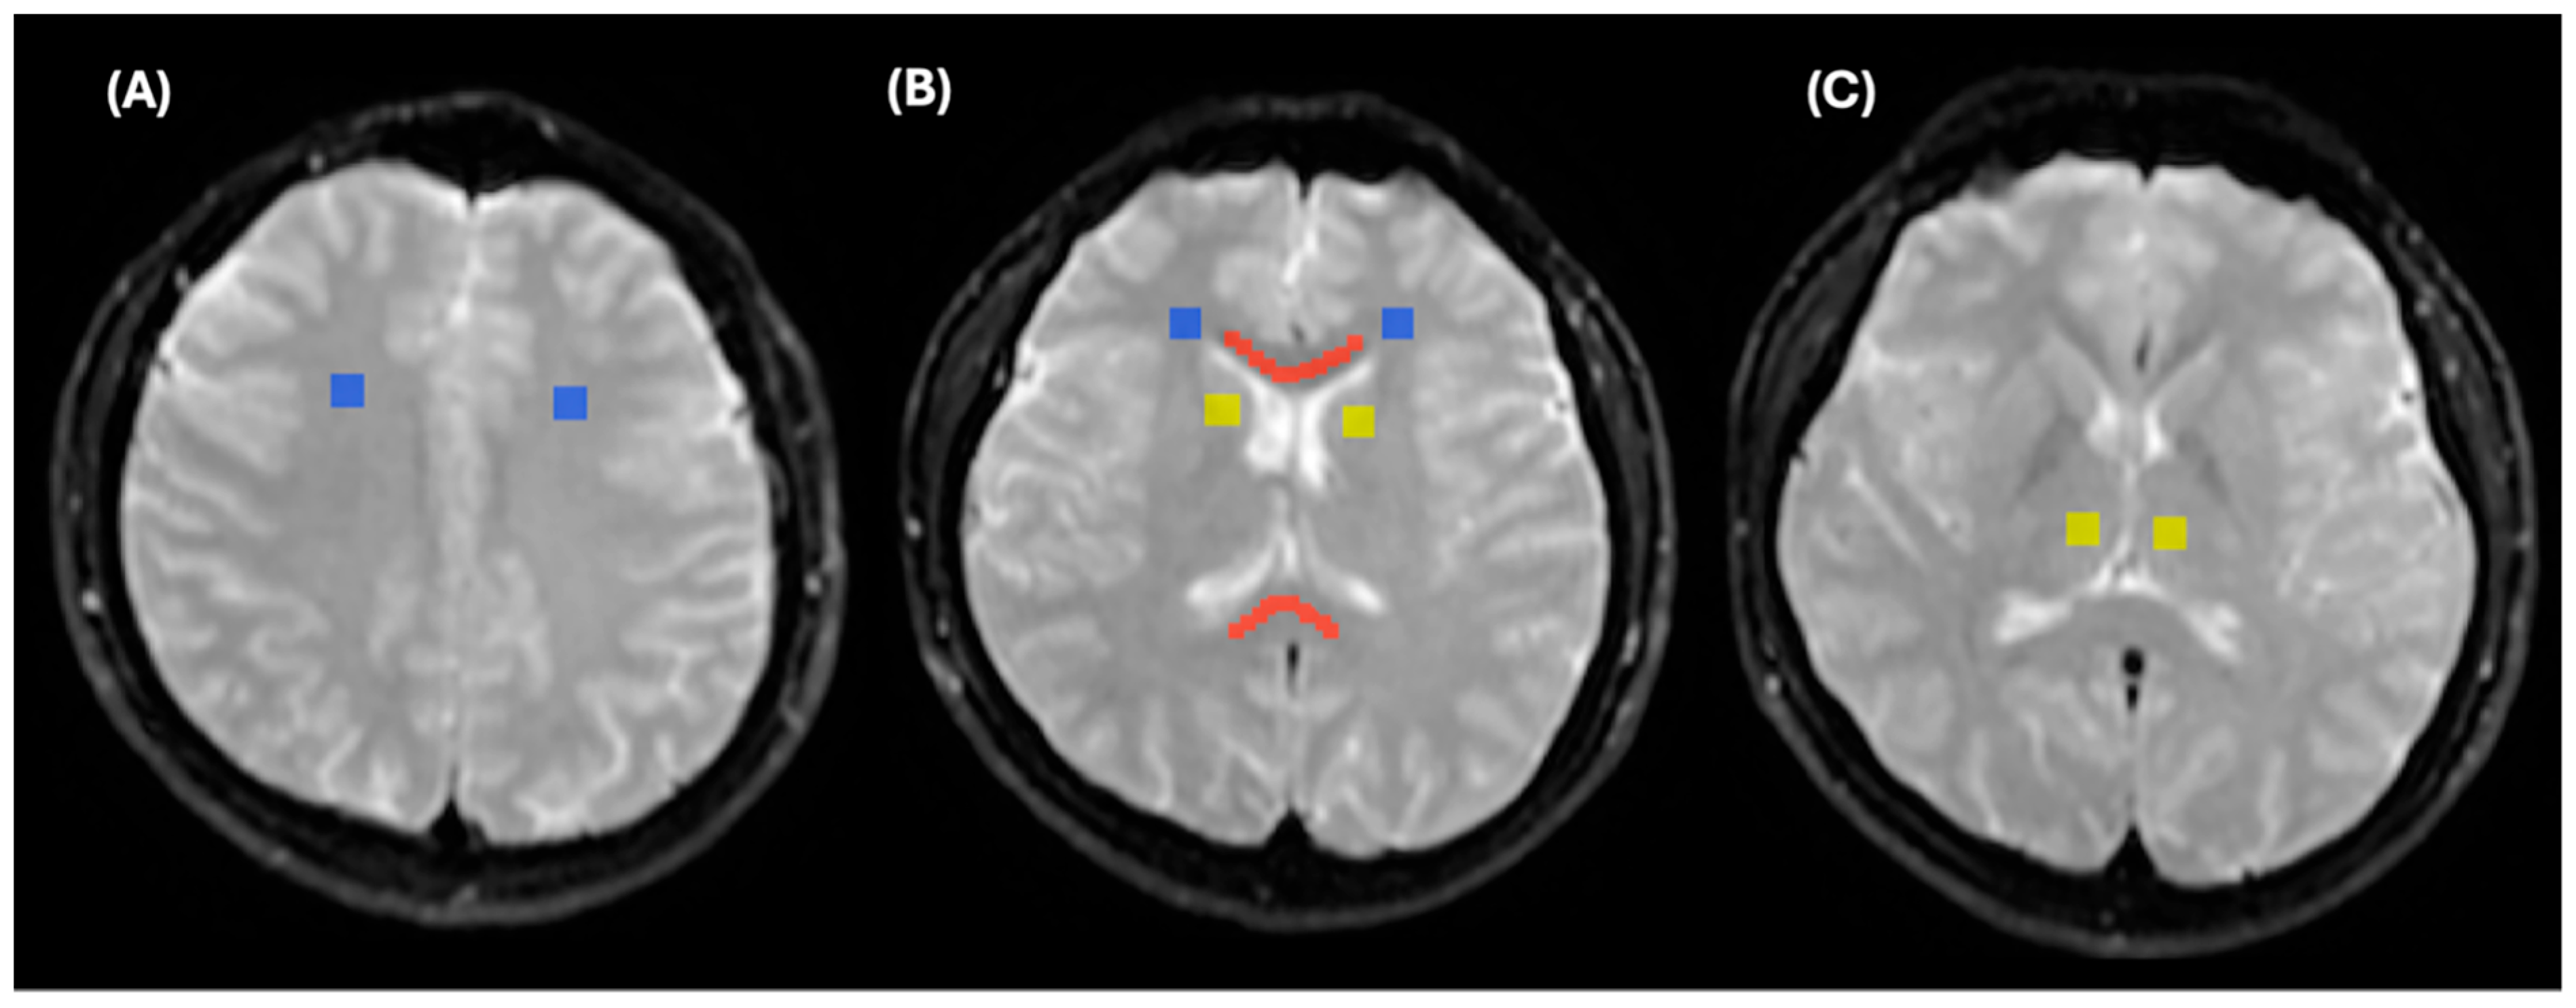

2.2. Lesion Analysis

2.4. MRI Processing